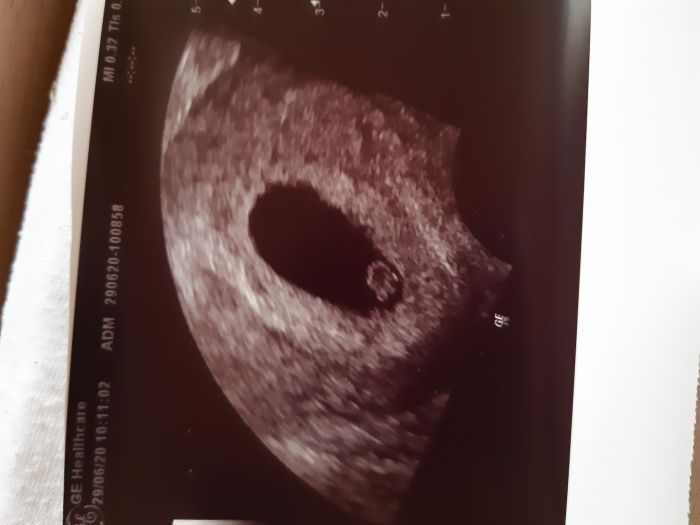

Ahoj holky, tak budeme mít třetí štěstí :) dneska kontrola bylo už krásně vidět srdíčko :)